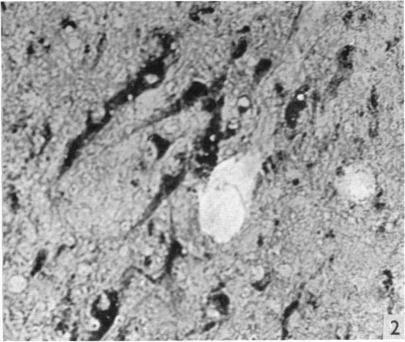

Hypothalamic neurosecretion in the dog and cat, with particular reference to the identification of neurosecretory material with posterior lobe hormone.

J Anat. 1955 Jul;89(3):301-16.